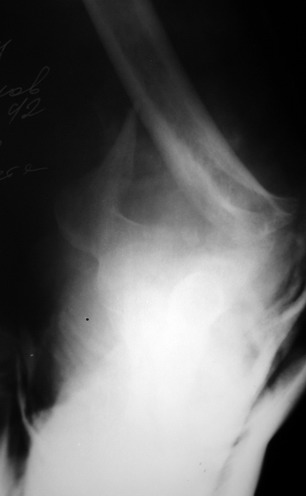

Женщина 42 лет, операция через неделю после перелома.

Д-з - открытый перелом мыщелков со смещзением и локтевой кости

без смещения - падение с лошади.

До операции снимки не очень, тем более в гипсе.